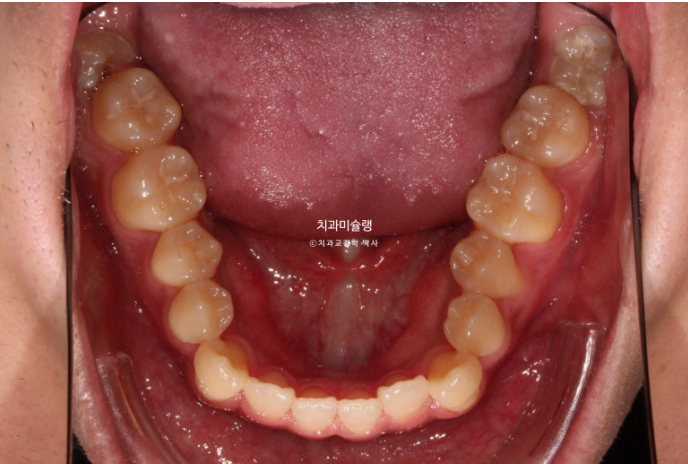

중심선이 어긋나있고 앞니 개방교합이 보입니다.

주걱턱으로 인해 앞니가 거꾸로 물리는 반대교합이 있습니다.

어금니 교합관계도 심한 3급입니다.

치료계획은 아래 사랑니 2개를 발치하고 사랑니 공간으로 치열을 뒤로 미는 것 입니다.

아래 앞니는 아래턱뼈 치조골 한계가 허용하는 극한까지 뒤로 들어갔습니다.

아래 어금니들은 가용한 사랑니 공간을 최대한 이용하며 뒤로 들어갔습니다.

2년 반동안 치근흡수도 없고 치근평행도는 좋습니다.